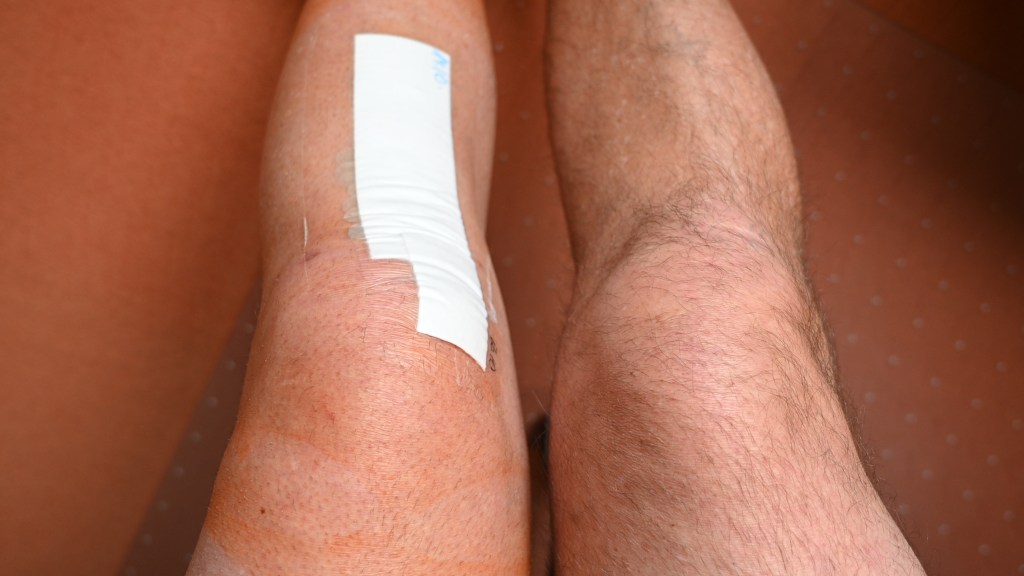

Die o. g. Frage haben sich bestimmt einige gestellt. Anhand der Zugriffszahlen in den letzten Wochen habe ich bemerkt, dass das Leben in meinem Blog scheinbar vermisst wird. Und es tut mir schon weh, dass ich momentan und auch in den nächsten Wochen nicht die Möglichkeit habe, sozusagen „fast live“ von den Barnimer Fußballplätzen zu berichten. Wer meinen Blog regelmäßig verfolgt, wird Anfang August diesen Eintrag (link) gelesen haben. Resultierend aus dieser Operation hat sich nun ein Folgeeingriff ergeben, der mich wiederholt in die Zwangspause gezwungen hat. Und diesmal noch deftiger als im August. Kurz erklärt, hat sich beim ersten Eingriff im Sommer ein Knorpelschaden vierten Grades im Innenbereich des Knies, gepaart mit einer Arthrose ergeben, welche eine Umstellungsosteotomie (HTO) des Knies durch eine Fehlstellung in der Beinachse erforderlich gemacht hat. Für Nichtmediziner einfach dargestellt: Ich hatte starke O-Beine und das Linke wurde nun begradigt. Hier sind drei Abbildungen, die einmal meine Beine im postoperativen Zustand zeigen und dazu zwei Fotos, auf denen zu sehen ist, was an meinem Unterschenkel gemacht wurde. Er ist „aufgekeilt“ worden und mit einer Metallplatte arretiert, so dass ich in Zukunft mehr mein Außenknie nutze, in dem noch einiges an Knorpelmaterial vorhanden ist. Klingt logisch, oder …?